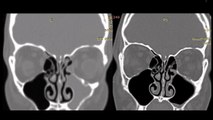

Körlemesine ağız içi kesiler tükürük bezi taşlı hastaların sialendoskopi ile tedavi şansını elinden alabiliyor. Ağız içi kesi yapılacaksa sialendopskopi eşliğinde, kanal onarımı ile beraber yapılmalıdır.

Detaylı bilgi için: https://atillasengor.net/s/tukuruk-bezi-tasi-tedavisi